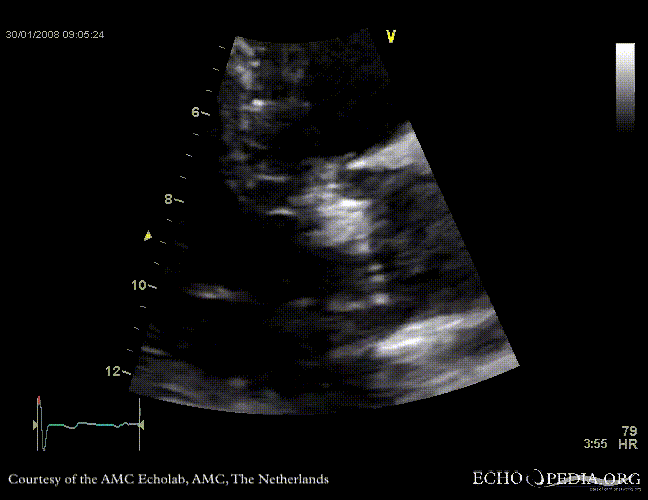

Aortic valve stenosis

AoS13